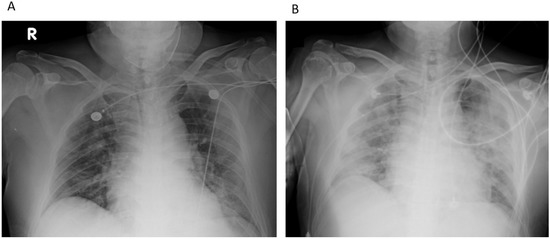

A 61-year-old man with chronic obstructive pulmonary disease history was admitted to the ED with dyspnea on exertion. Bilateral opacities were observed on chest radiography (Figure 2A). The patient had remarkable hypoxemia with oxygen saturation of 82% in room air (96% under a simple mask (10 L/min)). Remdesivir, dexamethasone, and empiric antibiotics (intravenous ceftaroline and oral azithromycin) were administered on admission. On Day 3, tocilizumab (6.25 mg/kg) was administered under the suspicion of cytokine release syndrome (C-reactive protein: 13.5 mg/dL; normal range: 0–0.79; LDH: 413 IU/L). Progressive hypoxemia (oxygen saturation approximately 91% under a non-rebreathing mask (15 L/min)) was observed within a few hours. The patient was intubated and transferred to the ICU for further treatment. The patient was placed in the prone position for 23 h because of persistent hypoxemia and the need for extremely high FiO2 after intubation. On Day 6, chest radiography revealed patchy opacities in the right lower lung and bilateral subcutaneous emphysema (Figure 2B). A muscle relaxant (cisatracurium) was administered, and the ventilator settings were adjusted by reducing the positive end-expiratory pressure from 12 to 7 mmHg and the tidal volume from 400 to 350 mL. For newly developed patchy opacities, antibiotics were switched to cefoperazone-sulbactam and levofloxacin for better nosocomial infection control. On Day 7, due to increased oxygen demand (FiO2 titrated up from 50% to 100%), the patient was placed in the prone position for 46 h before being switched to the supine position on Day 8. In the “dry lung” strategy, furosemide (20 mg) was administered intravenously twice daily because of the increased body weight and stationary chest X-ray. On Day 10, an empiric antifungal agent (voriconazole) [7] was administered for persistent hypoxemia, with a PaO2/FiO2 ratio of approximately 120, despite the absence of fever episodes. Laboratory data showed leukocytosis (112,000/uL) with left shift (band: 3%; segment: 87%; lymphocytes: 4%), elevated LDH (291 IU/L), elevated D-dimer (654 ng/mL), and elevated ferritin (1040.90 ng/mL). Blood and sputum cultures were repeatedly negative. The patient responded poorly to chest X-rays and oxygenation. A second dose of tocilizumab (3.1 mg/kg) was administered, and the antibiotic regimen was switched to intravenous meropenem, linezolid, and colistin on Day 11. After three days of observation, hypoxemia progressed, and the patient was placed in the prone position for 52 h on Day 14. Umbilical cord-derived mesenchymal stem cells were administered on Days 14 and 17. Micafungin was administered as “add-on” therapy [7]. On Day 18, sputum cultures (collected on Day 15) were positive for Ralstonia mannitolilytica. The blood Aspergillus antigen titer on Day 14 was 0.76. The antifungal agent was switched to intravenous posaconazole due to blurred vision, one of the common adverse effects of voriconazole [7]. After seven days of treatment, oxygenation improved, and the patient was extubated on Day 26. HFNC was continued; however, severe orthodeoxia (oxygen desaturation 85% while in the sitting position) occurred. After a short period of rehabilitation, the patient was transferred to the general ward on Day 36. Improvement was observed on a chest X-ray (Figure 2C), and the patient was discharged on Day 61.

Figure 2. Representative case 2 (Patient 5): (A) Bilateral opacities were observed on chest radiography taken in emergency department. (B) On Day 6, chest radiography revealed patchy opacities in the right lower lung and bilateral subcutaneous emphysema. (C) On Day 36, improvement was observed on chest X-ray.